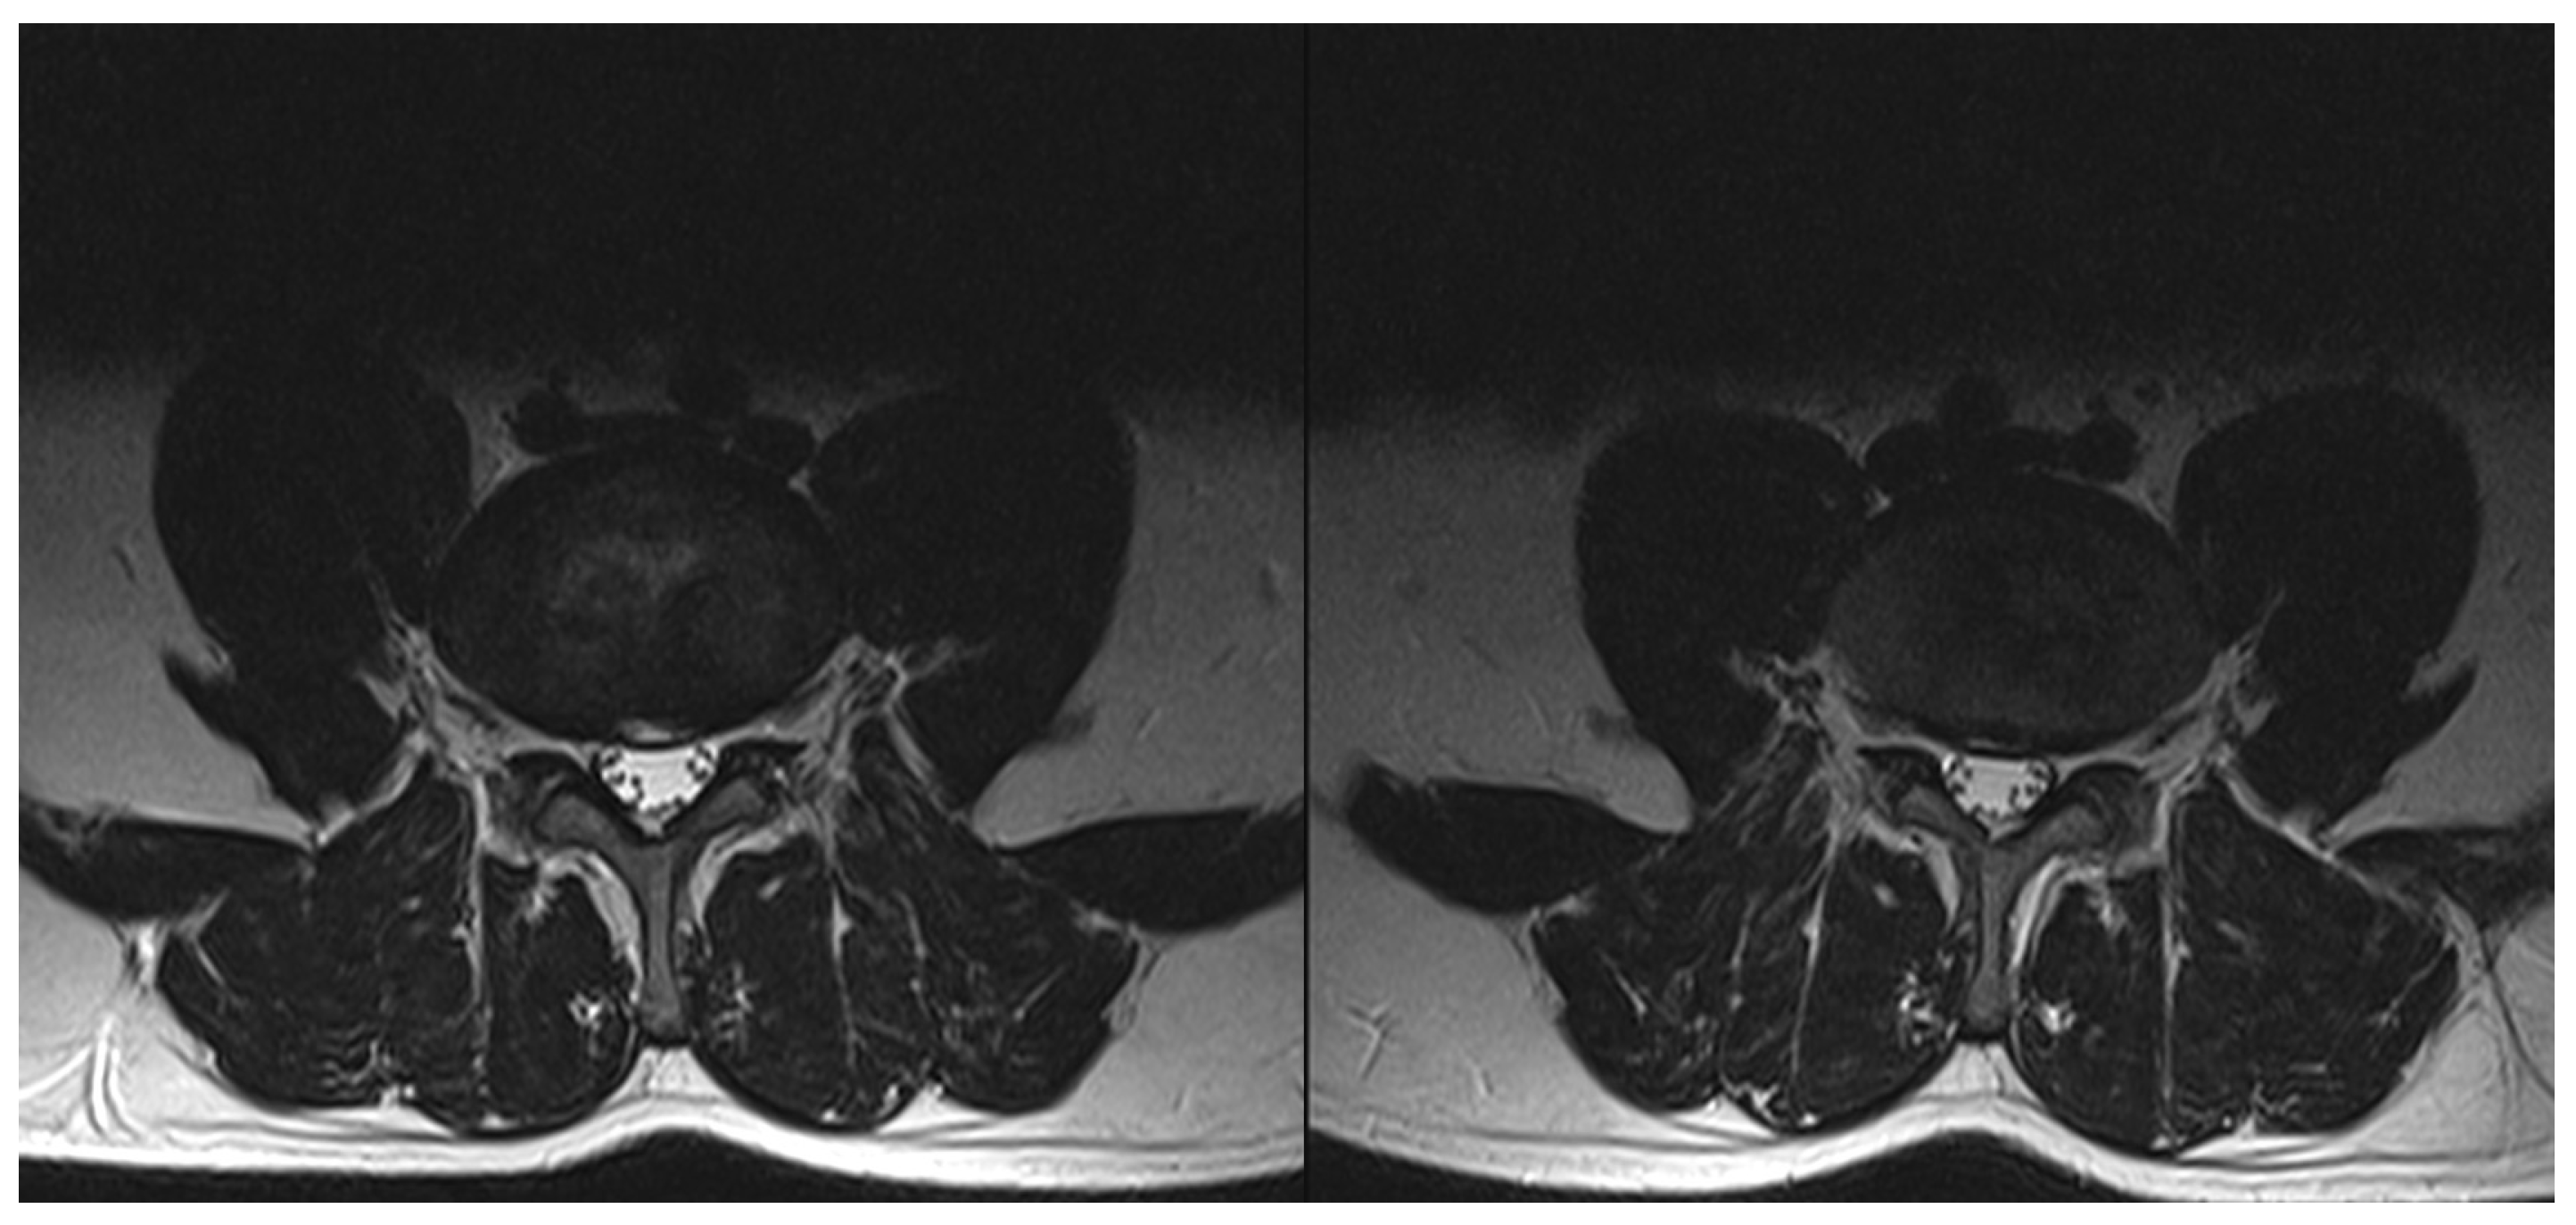

2.2. Procedure